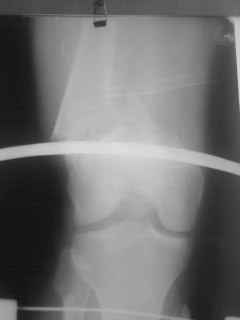

Уважаемые коллеги, прооперирована пациентка антеградным штифтом Остеомед, костная пластика не проводилась. Выбранный штифт по каналу бедренной кости на фоне отсутствия переднего кортикала в канале не центрируется. Технически неприятно, отсутствие передней и внутреннебоковой стенки до зоны мыщелков сильно затрудняло репозицию. Получилась вот такая картина. После стабилизации - очевидное повреждение ПКС и боковая нестабильность. В общем и далее будет чем заняться. Нам и в дальнейшем будет очень интересно мнение коллег.